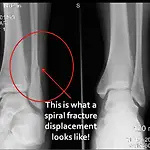

50대 남성분 골절, 골절 수술비 지급사례 사고일자 ; 2010년 8월 초 사고사항 ; 골절 수술 (출근시 계단에서 굴러 다리 골절로 수술받음) 피보험자 사항 ; 50대 초반 남성분 가입사항 ; 손해보험 (실손의료비 + 골절진단비 + 재해수술비 + 입원일당) 고객이 지급한 병원비 ; 약 150만원 치료기간 ; 수술전 입원포함 30일간 입원치료 보험금 지급내역 ; 골절진단 30만원 + 골절수술비 100만원 + 입원비 포함 병원비 지급 (다른 보험사에 운전자 보험중 상해의료비가 중복되어 비례보상됨) 합계 ; 약 260만원 지급 완료 **주의할점** 실손의료비 특약은 실제 손해난 부분에 대해서 보장을 해드리는 특약으로 다른 보험사에 유사한 특약이 있을경우 비례 보상되는 부분을 꼭 유념하시기 바람. 2010/0..